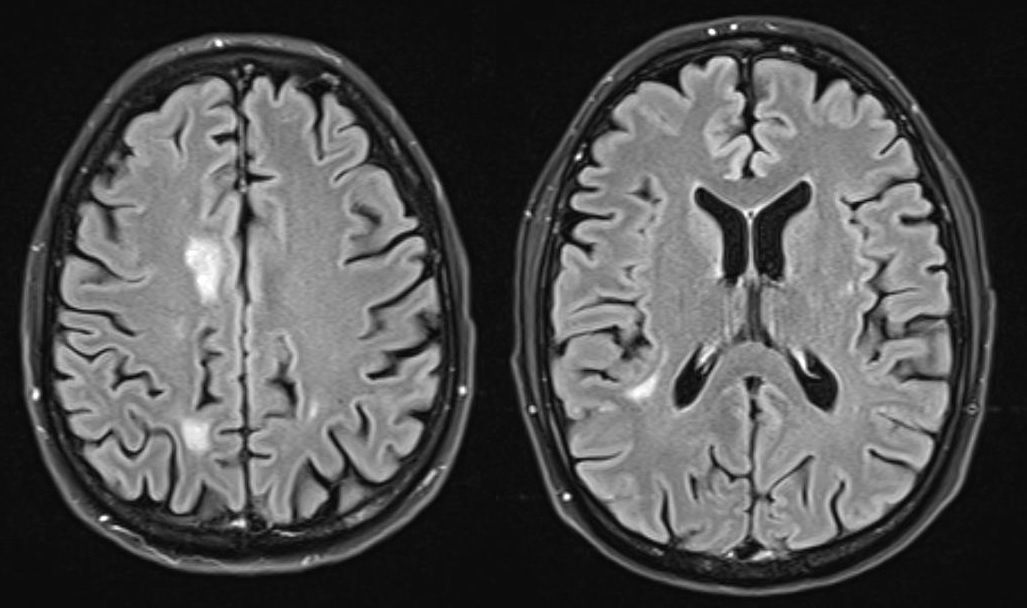

Introduction: This case report describes a serious complication of delayed human immunodeficiency virus (HIV) diagnosis in a patient initially misdiagnosed with palliative-stage cancer and subsequently diagnosed with B-cell lymphoma. This situation highlights the diagnostic challenges and treatment implications following HIV diagnosis, and underscores the critical importance of accurate and timely HIV detection in oncology patients.

Case presentation: A 39-year-old man was initially diagnosed with lung cancer based on computed tomography and histopathologic findings. He was treated with 2 lines of chemotherapy over an 8-month period, the neoplastic lung lesions progressed, and he was referred to palliative care. Two years after his initial diagnosis, during the management of an actively bleeding gastric tumor, he was diagnosed with HIV and referred to an infectious disease unit. Immediate antiretroviral treatment was initiated after diagnosis, and further evaluation confirmed the presence of B-cell lymphoma. A retrospective review suggested that the initial cancer diagnosis was likely misinterpreted and was in fact lymphoma, a malignancy commonly associated with HIV. Lymphoma treatment was initiated, and after 1 year, the patient achieved HIV-1 virologic suppression and near-complete remission of all lesions.